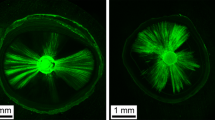

The prepared discs were stained using a Live and Dead Bacterial Viability kit (L-7012 Molecular Probes; Eugene, OR, USA), which consists of two separate vials of two-component dyes (propidium iodide and SYTO9 mixed 1:1) for staining the bacteria. The dyes had excitation/emission maxima of 490–635 nm for propidium iodide, which stained dead bacteria in red, and 480–500 nm for SYTO 9, which stained active bacteria in green [26]. Following staining, the specimens were examined by CLSM (Leica DMi8; Leica Microsystems CMS GmbH, Germany). Single-channel imaging was used to display green and red fluorescence separately, after which the two channels were merged using LAS X software (version 1.1.0.12420; Leica Microsystems CMS GmbH). CLSM images of the bacteria within infected dentinal tubules were captured at a resolution of 1024 × 1024 pixels, and the specimens were assessed using ×5 and ×10 lenses.

Descriptive analysis of Confocal Laser microscopic images

The CLSM (×5 and ×10 magnification) images revealed viable bacterial penetration in all the positive control group specimens by the green fluorescence. Meanwhile all the negative control group specimens showed no fluorescence because of the absolute absence of bacteria.

For the three experimental groups, the red fluorescence indicating dead bacteria was the prominent feature seen with no visible difference in the distribution of the dead bacteria. Although minute spots of green fluorescence where detected nearby the root canal lumen (Figs. 5 and 6).

(a-f): demonstrating images from confocal laser scanning microscopy (CLSM) (magnification scale; a: 0–500 μm, b–f: 0–250 μm), of the E.fecalis bacterial penetration into the dentinal tubules of experimental group specimens .Green displays live bacteria(f), red displays dead bacteria (e).The bacteria can be presented at high (b-f) and low magnification (a)